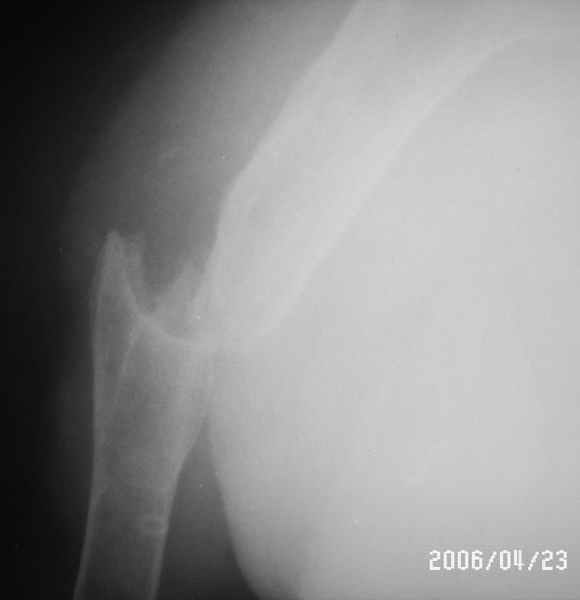

Уважаемые коллеги! Помогите в выборе тактики лечения больной Р.,56 лет, с болтающимся ложным суставом с/3 правой плечевой кости 2-х летней давности. В анамнезе - бронхиальная астма, гормонозависимая форма, ожирение III cт. Травма - автодорожная, получила закрытый многооскольчатый перелом диафиза плечевой кости со смещением (от метафиза до метафиза), в экстренном порядке нами произведен закрытый остеосинтез стержневым аппаратом, отломки удалось сопоставить анатомически. В дальнейшем больная выпала из поля зрения. Как потом выяснилось, после снятия стержневого аппарата, больная долечивалась по Илизарову специалистом из г. Кургана. Аппарат Илизарова удален из-за нагноения мягких тканей. Последние два года работая бухгалтером, фиксирует плечо ортезом. Теперь вновь обратилась к нам для ликвидации ложного сустава.

Есть вариант открытого вмешательства с резекцией зоны ложного сустава, костной пластикой и накостным остеосинтезом хорошей пластиной, в смысле мощной и длинной.